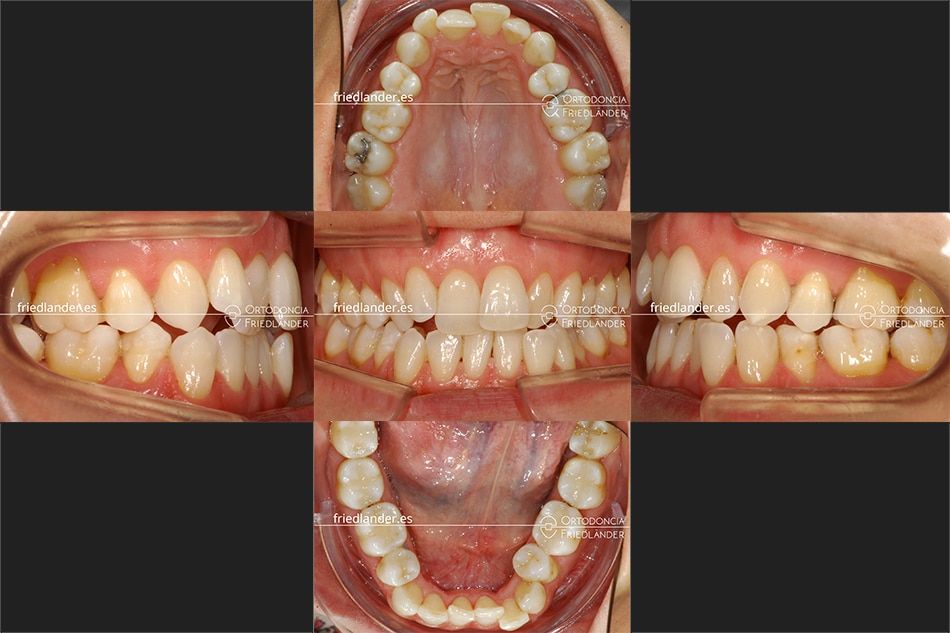

Este caso es un retratamiento, es decir, un tratamiento de una recidiva de un antiguo tratamiento de ortodoncia. La paciente de 39 años acude a la consulta en busca de solución para su maloclusión comentando que en los últimos años los dientes se le han movido mucho y que le cuesta mucho masticar, quiere volver a tener los dientes en buena posición.

En la exploración clínica, de la primera visita, se podía observar una maloclusión de clase II, mordida abierta, apiñamiento moderado, arcadas estrechas (los dientes posteriores están inclinados hacia dentro de la boca), los márgenes gingivales de los dientes anteriores están desnivelados y por último presenta unas encías delicadas de biotipo fino con varios dientes con recesiones gingivales. La paciente no comentó que no quería volver a llevar brackets bajo ningún concepto y solamente quiere tratarse con Invisalign por sus múltiples ventajas.

El tratamiento se realizó con distalización de la arcada superior, stripping y elásticos de clase II. En la siguiente imagen se puede ver el resultado a los 18 meses de tratamiento